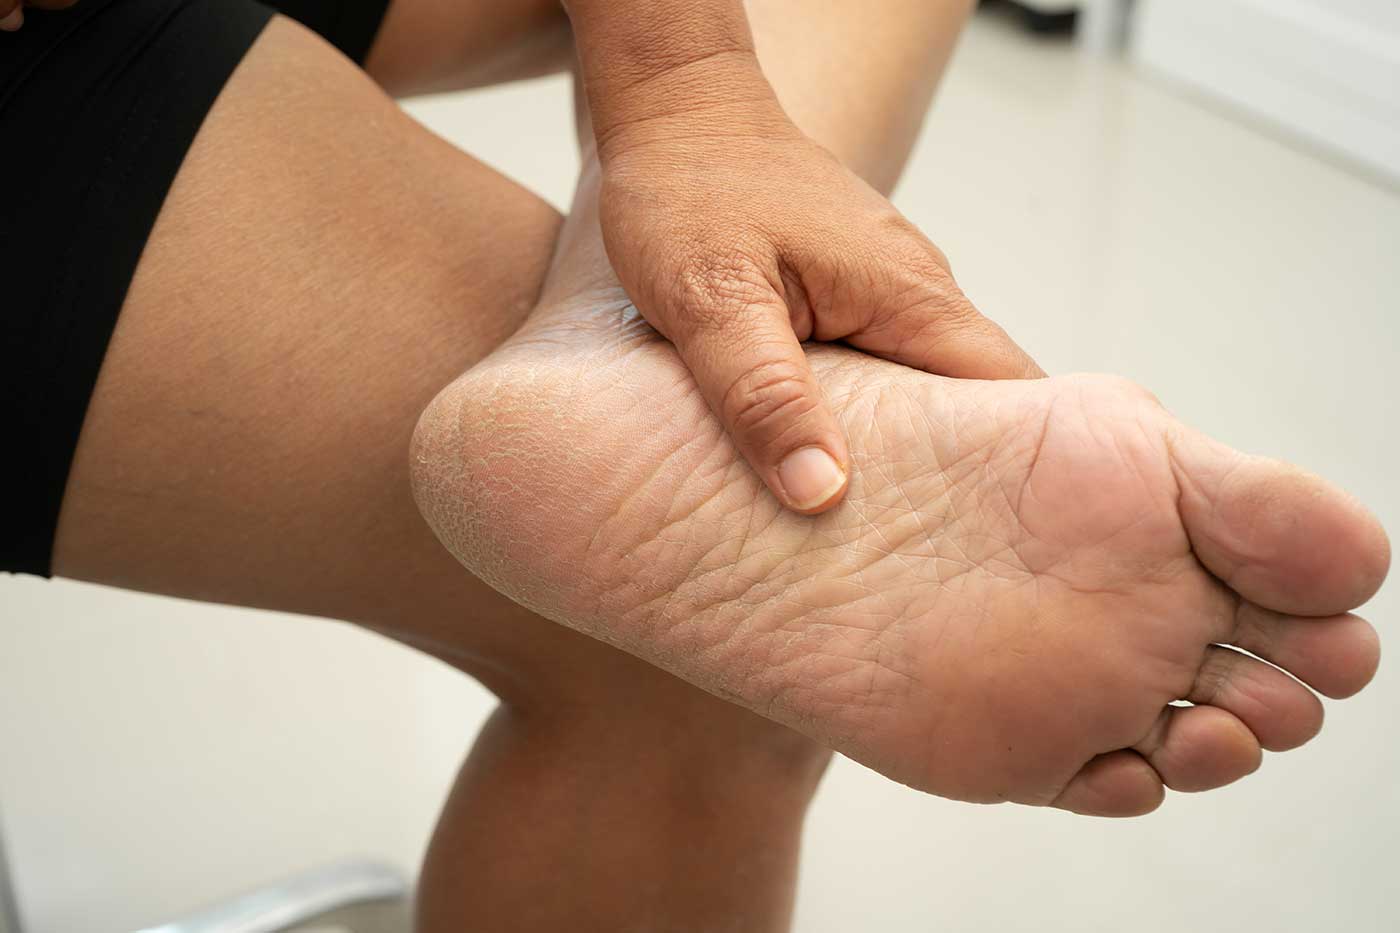

Een hielspoor is een ontsteking van een pees onder de hiel [1]. In sommige literatuur wordt er ook wel verwezen naar een extra stukje bot dat soms ontstaat onder de hak/hiel. In de volksmond noemt men klachten onder de voet al snel een hielspoor.

Wanneer de pees ontstoken is (fasciitis plantaris), ervaart men pijnklachten onder de voet. Vaak is deze pijn zeurend, maar soms kan het ook stekend zijn. De klachten beginnen vaak langzaam, en in het begin heb je alleen last na een lange wandeling.

Naarmate de klachten toenemen, kun je zelfs bij normaal lopen pijn ervaren onder de voet. ’s Ochtends is de voet vaak stijf en aan het einde van de dag extra gevoelig.